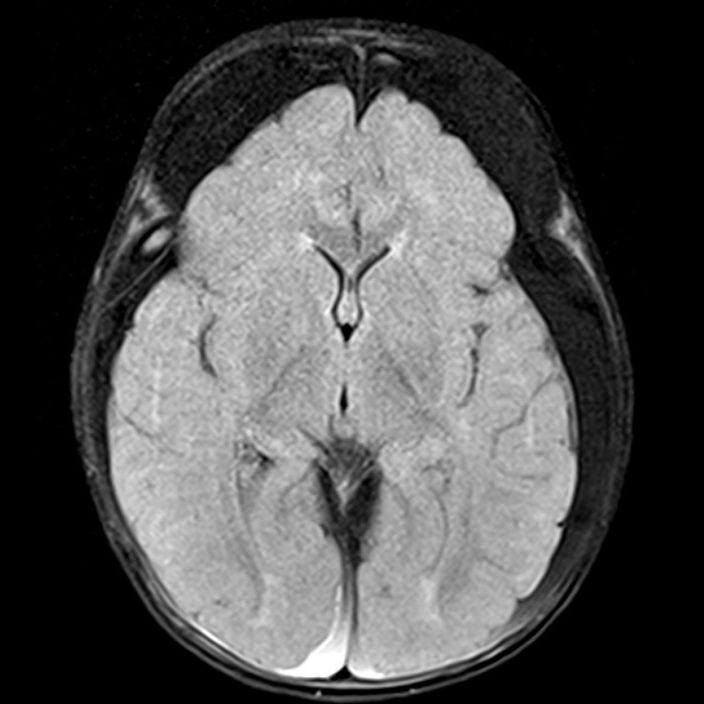

- A) Bilateral serebral konveksitede subdural higroma

- D) Posteriyor fossada subdural hemoraji

- Subdural hematom: En sık görülen radyolojik bulgudur, vakaların %83-90’ında saptanır. Genellikle bilateraldir ve farklı yaşlarda hemorajik elemanlar içerir.

- Subaraknoid kanama: Hastaların yaklaşık %30’unda saptanır. En sık frontal, parietal ve temporal bölgelerde görülür ve sıklıkla birden fazla bölgeyi ilgilendirir.

- Subdural higroma: Araknoid yırtıklara bağlı gelişir. Köprü ven yaralanması ile birlikte olduğunda hemorajik bileşenler içerebilir (hematohigroma).